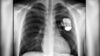

Kicker mit Kunstherz

Köln, Nur dank dieses Defibrillators lebt Daniel Engelbrecht aus Köln noch. Das Schockgerät wurde dem Fußballprofi nach einer Herzattacke vor vier Jahren eingesetzt. Damit war er weltweit der erste Fußballer, der mit diesem Hilfsmittel gespielt hat. weiter…